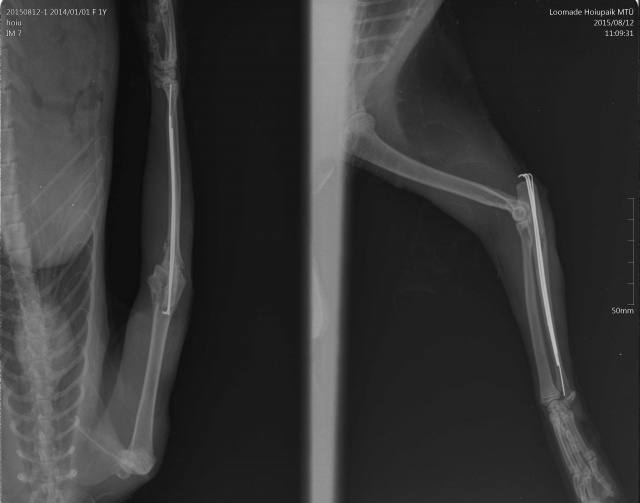

Диагноз:

- вывих локтевого сустава

- перелом локтевой кости

- межмыщелковый перелом плеча(?)

Esikäpa vigastusega.